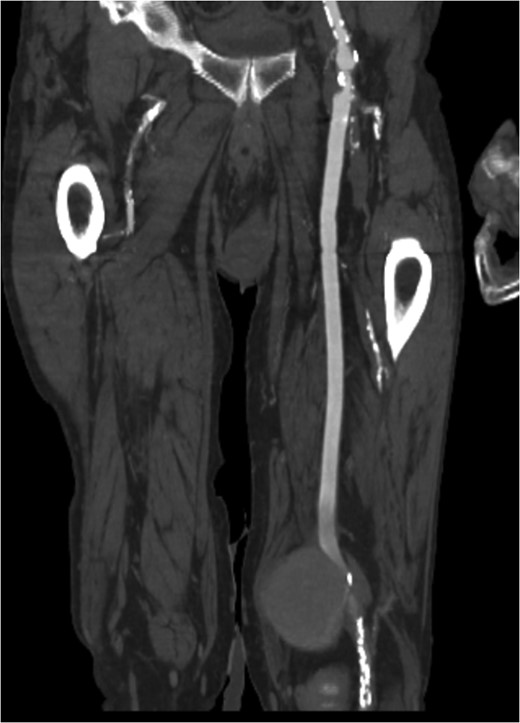

Coronal view of popliteal PS of distal anastomosis site of femoral–popliteal bypass.

Pseudoaneurysm (PA) following vascular reconstruction is a complication of bypass surgery. Historically, the mainstay of treatment was an open repair; the surgical management consisted of resection of the initial graft with reimplantation of a new bypass either into the original arteriotomy or to a more distal target. Placement of a stent graft to exclude the PA is a viable option. We present a case of an 85-year-old man with prior history of polytetrafluoroethylene femoral–popliteal bypass now with an 8 × 5.6 cm PA of the distal anastomosis site treated with endovascular placement of a Viabahn stent.

Pseudoaneurysm (PA) formation has been described in the literature as a delayed presentation in surgically revascularized patients. Given the rising number of reconstructive vascular procedures, the increase in anastomotic PA cases is expected [1]. Potential degeneration of biosynthetic grafts with aneurysm formation is a well-known problem with a reported incidence of up to 7% [2]. Implantation of a stent graft for treatment of a PA is a valuable treatment option in native arteries, as well as bypass grafts, as reported by Magnetti et al. [2]. In high-surgical-risk patients, the placement of a stent graft provides a safe and effective option for the treatment of anastomotic PA. We present a case of an 85-year-old man with prior history of polytetrafluoroethylene (PTFE) femoral–popliteal bypass now with an 8 × 5.6 cm PA of the distal anastomosis site treated with endovascular placement of a Viabahn stent. Of note, the patient underwent open thrombectomy and patch angioplasty of the site 10 years prior. Proper written consent was obtained from the patient prior to the creation of this case report.